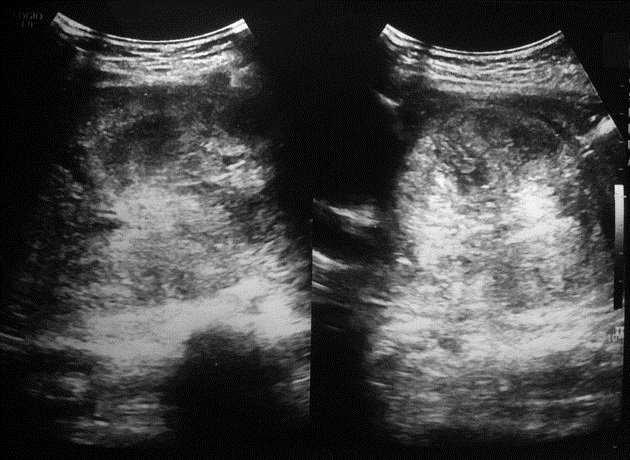

Image echographique d'une

tumeur

pseudo-papillaire et solide du pancreas (

tumeur de Franzt ) de grand taille

avec aspect lesionnel de masse tumorale hypoechogen

, heterogene en association des formations kystiques

aechogenes |

Une autre cas de tumeur de

Franzt tres volumineuse , a bord circoncrete nette

hypoechogen et heterogene . Image echographique

percutanee abdominale , coupe transverse |